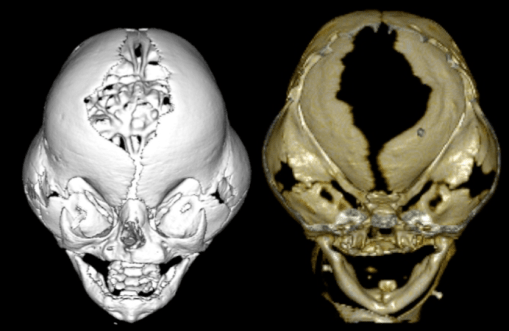

on note le contraste entre le bombement de l’os frontal et des écailles temporales, et le creux correspondant aux sutures coronales, d’où l’aspect en trèfle.

imagerie

- le scanner montre la fermeture des sutures, les lacunes osseuses, la compression des structures intracrâniennes, l’hydrocéphalie